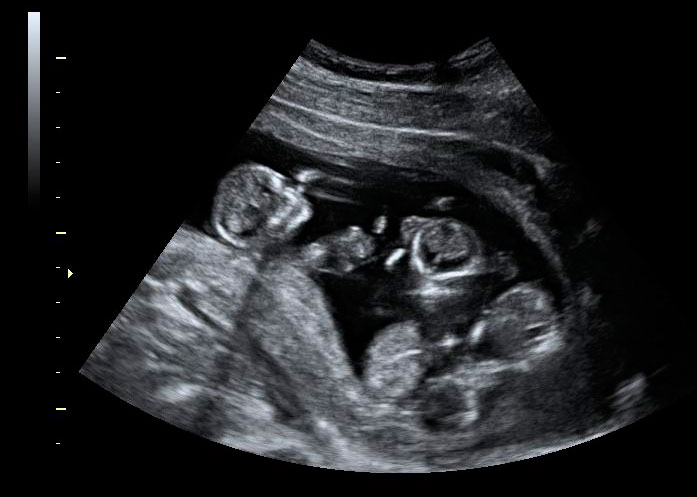

Imagen de trillizos de 13 semanas en ecografía 3D

En esta imagen en 3D muestra trillizos de 13 semanas. La ecografía nos informa de un hermano independiente, separado por una membrana de sus hermanos, que son gemelos. A su vez, los gemelos están separados, en bolsas independientes, por una membrana más fina. La gestación de trillizos es un embarazo de alto riesgo que ha de ser controlado muy de cerca por el ginecólogo.